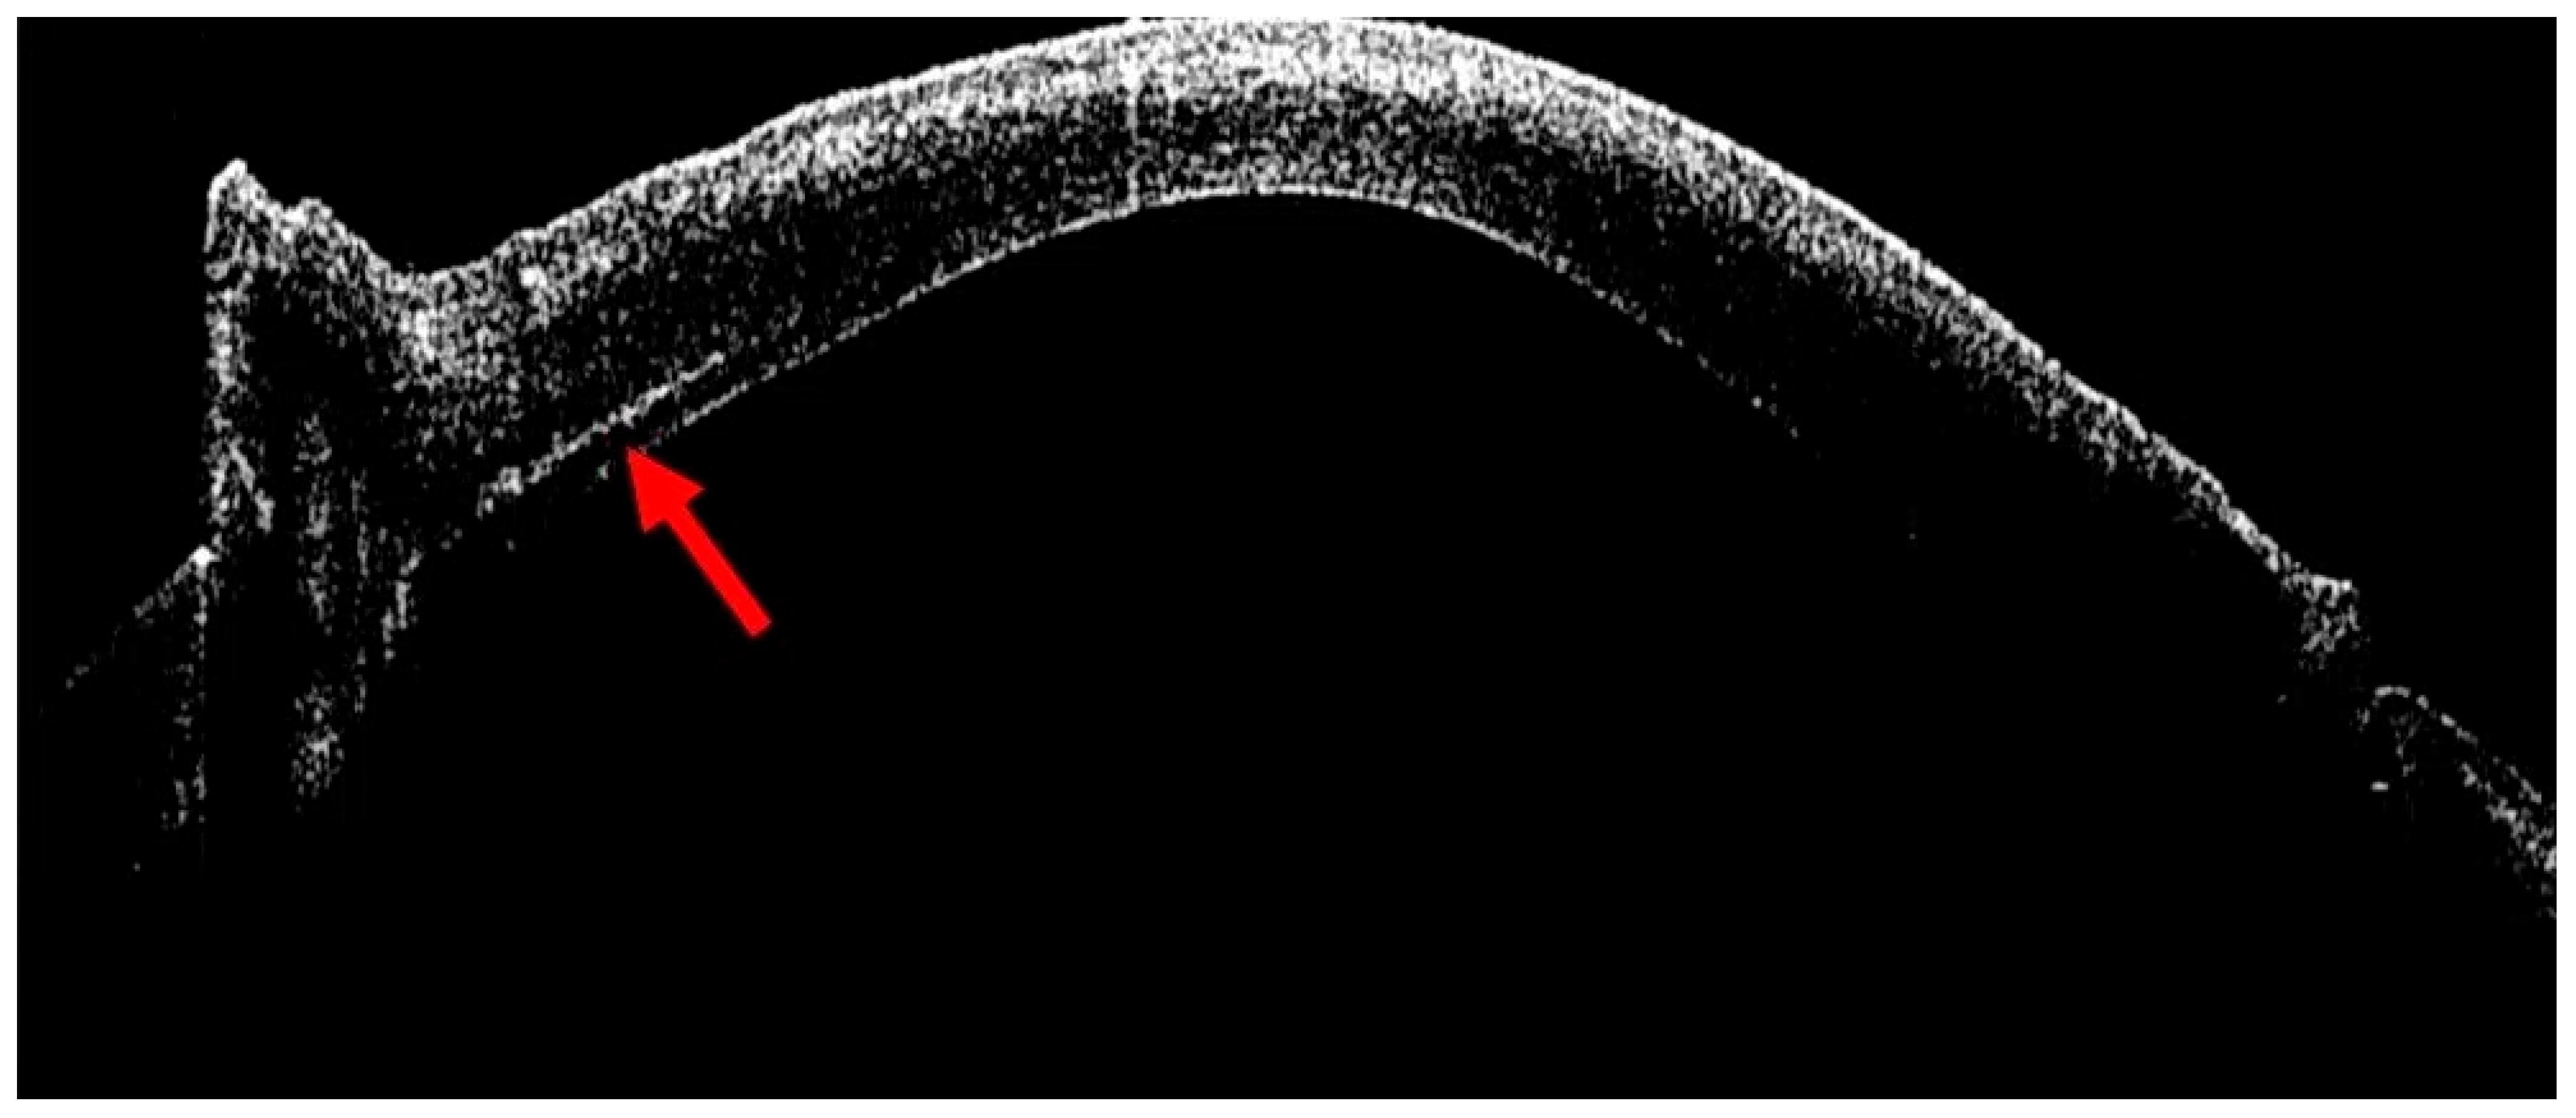

- Moramarco, A.; Elifani, M.; Zimbru, M.S.; Rosolia, A.; Mete, M.; Fontana, L. Air-Assisted Dome Drainage in Acute Corneal Hydrops: A 3D-OCT-Guided Approach. Bioengineering 2025, 12, 867. [Google Scholar] [CrossRef] [PubMed]

- Siebelmann, S.; Händel, A.; Matthaei, M.; Bachmann, B.; Cursiefen, C. Microscope-Integrated Optical Coherence Tomography-Guided Drainage of Acute Corneal Hydrops in Keratoconus Combined With Suturing and Gas-Aided Reattachment of Descemet Membrane. Cornea 2019, 38, 1058–1061. [Google Scholar] [CrossRef]

- Kaur, M.; Balaji, A.; Titiyal, J.S.; Bansal, M.; Raj, R.; Namdev, V. Intraoperative optical coherence tomography-guided compression sutures in acute corneal hydrops-Surgical technique and review of literature. Indian J. Ophthalmol. 2025. Epub ahead of print. [Google Scholar] [CrossRef] [PubMed]

| Moramarco et al. [29] | Case series | 6 eyes | Corneal hydrops drainage | Controlled drainage of the stromal dome with a 23-gauge sclerotome, with dynamic monitoring of fluid outflow |

| Siebelmann et al. [30] | Case series | 2 patients | Corneal hydrops drainage | iOCT-guided puncture and drainage of intrastromal fluid pockets combined with anterior chamber sulfur hexafluoride-fill and pre-descemetic sutures |

| Kaur et al. [31] | Prospective interventional case series | 7 patients | Corneal hydrops drainage | Assess the morphological features of the hydrops, titrate the magnitude of suture tightness and confirm the depth of suture placement |